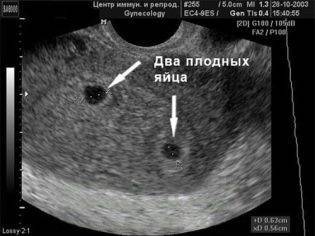

Нередко во время обследования врач-узист может обнаружить второе плодное яйцо. В этом случае женщину можно поздравить, так как у нее будет рождение двойни. Такая беременность развивается, когда происходит одновременное оплодотворение двух яйцеклеток или развитие двух зигот из одного и того же яйца.

Если женщина ожидает двойню, то плодное яйцо в момент деления может сформировать одну или две плаценты.

Если момент прикрепления яйца к матке происходит после 8-13 суток от дня оплодотворения, то формируются 2 плода и одна плацента на двоих. Это значит, что оба плода будут развиваться в одном плодном пузыре. Если же деление происходит ранее этого срока, то каждый эмбрион будет развиваться в своем плодном яйце.